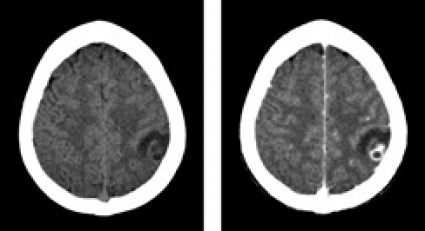

Datortomografi (DT) och magnetresonanstomografi (MRT) påvisade en solitär, drygt 1 cm stor rundad lesion i övergången mellan vit substans och kortex parietalt i vänster hjärnhalva. Förändringen var omgiven av en kontrastuppladdande kapsel och av ett ödem, som sträckte sig över hela den främre delen av vänster hemisfär (Figur 1 och Figur 2).

Differentialdiagnosen ur neuroradiologisk synvinkel omfattade bakteriell hjärnabscess och parasitinfektion, främst neurocysticerkos, men neoplasi (hjärntumör eller tumörmetastas) kunde inte med säkerhet uteslutas. Bilderna förmedlades via patientens familj till flera neurokirurger i patientens hemland, som samstämmigt ansåg att neurocysticerkos var mest sannolikt. I cerebrospinalvätska var antalet av polynukleära leukocyter diskret förhöjt (2,5 106/l). Western blot-analys av serum och cerebrospinalvätska påvisade inga antikroppar mot Taenia solium. Serologi för Toxoplasma gondii var negativ. I fecesdirektmikroskopi och i tejpprov fann man inga maskägg. Normalt ögonfynd konstaterades vid ögonläkarundersökning. Ett elektroencefalogram visade diffus förlångsamning med vänstersidig övervikt.

Nästa steg är en DT- eller hellre en MRT-undersökning av hjärnan. Fynden i DT kan vara relativt ospecifika medan MRT ger bättre information om cystans innehåll. Vid neurocysticerkos ser man en eller flera cystor med kontrastladdande rand. Ibland kan parasitens skolex identifieras som en millimeterstor punkt, vilket gäller som ett säkert diagnostiskt tecken [6]. Äldre cystor förkalkas. Om den radiologiska undersökningen visar en patologi förenlig med neurocysticerkos analyseras serum eller cerebrospinalvätska med antikroppstest (immunblot-teknik enligt Tsang [7]). I Sverige utförs testet inte rutinmässigt, men prov kan lämnas till Smittskyddsinstitutet, som vidarebefordrar det till Schweiz. Testets specificitet anges till 100 procent, medan sensitiviteten varierar: upp till 95 procent vid multipla, icke-förkalkade intracerebrala lesioner och enbart ca 50–80 procent vid solitära cystor. Testet kan inte skilja mellan aktuell och genomgången infektion. Eosinofili i cerebrospinalvätska (men inte i blod) kan tyda på neurocysticerkos; differentialräkning av celler i cerebrospinalvätska kan genomföras manuellt i ett färskt likvorprov.

Anamnesen och den radiologiska bilden gjorde att den kliniska misstanken om neurocysticerkos var relativt stark. Däremot var de radiologiska förändringarna inte entydiga, någon skolex kunde inte identifieras. Dessutom var serologin negativ, och i likvor fanns en lätt pleocytos.